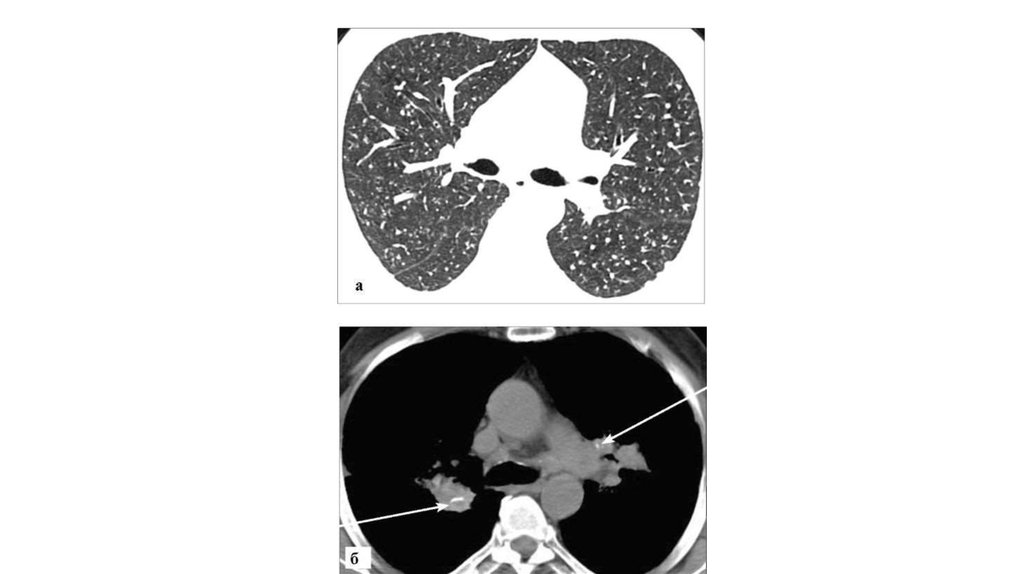

• Силикоз. КТ:

• а - режим «легочного окна». В обоих легких определяются

множественные мелкие, четко очерченные узелки на фоне

умеренных интерстициальных изменений; б - мягкотканый

режим. Видны очаговые обызвествления внутри увеличенных

бронхопульмональных лимфоузлов (стрелки)